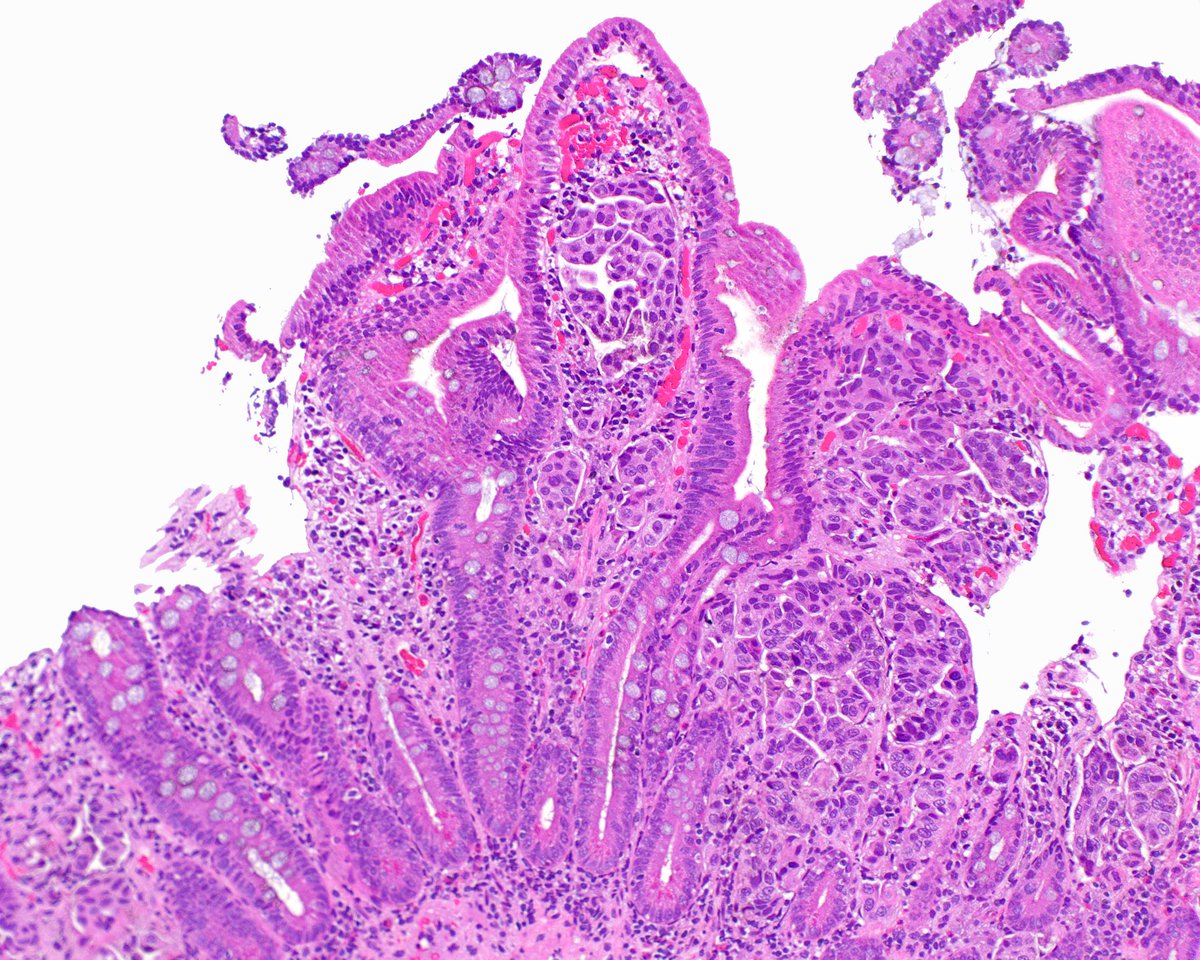

Great to catch up with @ESadimin during #KCRS2024. “It’s all about negative margins.” @CityofHope_GU @OSUCCC_James @OSU_Urology

Pathologist at City of Hope specializing in clinical informatics and urological pathology